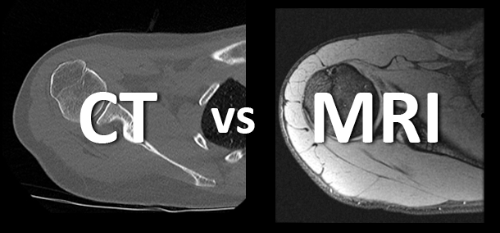

3.CT(전산화 단층촬영)

흉부 CT 촬영은 흉부 엑스레이보다 폐암을 발견할 수 있는 확률이 높고 이로 인해 폐암을 조기 발견하여 사망률은 낮출 수 있습니다. 저선량 CT는 방사선 조사량을 기존 CT에 비해 현저하게 줄이는 검사 방법으로 방사선에 노출되는 위험을 줄일 수 있습니다. 이 검사 방법은 해상도는 저선량이라서 기존 CT에 비하여 감소하지만 병변 유무를 관찰하는 데는 충분하며 간편한 검사입니다. X-ray에서 발견이 어려운 초기 폐암의 경우 흉부 CT 촬영을 통해 조기에 발견할 수 있습니다.

5. MRI (자기공명영상)

자기공명영상(MRI)은 폐암 진단에도 활용될 수 있습니다. 또한 수술을 위해 종양의 구체적인 위치를 확인해야 하는 경우에 이 검사를 하게 됩니다. MRI는 보통 신체 구조에 대한 데이터를 모으는 검사 방법입니다. 이 검사를 통해서 최소한의 체내 조직 변화와 문제가 되는 곳의 정확한 위치를 확인할 수 있습니다. 그리고 MRI는 방사선에 노출될 위험이 없고 검사를 위해 조영제가 필요하지 않습니다. 하지만 MRI는 자기공명요법이 무선파와 자기력을 이용하여 검사가 진행되기 때문에 폐쇄공포증이 있거나 심장박동기를 장착한 경우라면 문제가 될 수 있습니다.